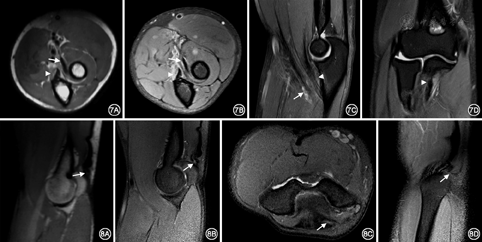

38例肘关节外伤患者,44条肌腱损伤,其中伸肌总腱损伤14例(6例伴桡侧副韧带损伤,2例伴肘关节骨折及桡侧副韧带损伤,1例伴肘关节脱位、尺侧副韧带及外侧副韧带复合体损伤,1例伴尺侧副韧带损伤),MR表现为伸肌总腱肱骨外上髁附着处部分纤维走形不连续性,PD-FS序列信号增高,局部被液体充填(图4)。屈肌总腱损伤10例(1例伴肘关节脱位、尺侧副韧带及外侧副韧带复合体损伤,3例伴尺侧副韧带损伤,1例伴肘关节脱位及环状韧带损伤),MR表现为纤维走形连续性不佳,T1WI序列呈低信号,PD-FS序列呈高信号,其周围软组织水肿(图5)。肱二头肌腱损伤3例(2例伴肘关节脱位、尺侧副韧带及外侧副韧带复合体损伤),MR表现为肱二头肌腱远端迂曲增粗,部分纤维不连续,桡骨粗隆附着点处T1WI序列呈低信号,PD-FS序列呈高信号改变,伴桡骨头脱位,骨髓及周围软组织水肿,关节腔积液(图6)。肱肌肌腱损伤7例(1例伴尺侧副韧带损伤,1例伴肘关节骨折,伴肘关节脱位及环状韧带损伤1例),MRI表现为肱肌腱尺骨粗隆附着端迂曲,T1WI序列呈水样低信号,PD-FS序列腱鞘走行区内信号增高,腱鞘积液(图7)。肱三头肌腱损伤10例(其中1例伴有骨折),MR表现为肱三头肌腱远端长头和外侧头部分撕裂,表现为迂曲增粗,鹰嘴附着端部分纤维不连续,T1WI序列纤维增粗,形态不规则,呈低信号改变,PD-FS序列肌纤维迂曲增粗,其内可见条状高信号改变,为纤维部分撕裂被液体充填所致(图8)。

通常采用冠状位观察屈肌总腱和伸肌总腱的走行。文献报道[7,8],屈肌总腱和伸肌总腱损伤时常伴有同侧副韧带的损伤。本研究中,14例伸肌总腱损伤患者中,10例伴桡侧副韧带损伤,10例屈肌总腱损伤者,4例伴尺侧副韧带损伤,因此,冠状位观察屈、伸肌总腱损伤时,应仔细检查是否伴有邻近侧副韧带的损伤,如果忽视侧副韧带的损伤,患者在行肌腱松解术之后肘关节会更不稳定,使症状加重,造成严重肘关节功能障碍。轴位主要观察肱二头肌腱及肱肌腱形态以及是否有纵向撕裂或腱鞘积液[9]。肱二头肌腱损伤以部分撕裂最常见,关于肱二头肌腱损伤的报道尚不多见,且常被忽视和漏诊,而延误诊断和治疗[10]。当发生肱二头肌腱和肱肌腱损伤时,通常发生在肌腱远端的附着端,因此,扫描范围必须包括桡骨粗隆,采用矢状位和轴位观察,可清晰显示肱二头肌腱和肱肌腱的桡骨和尺骨附着端以及明确肌腱损伤情况。在急性期临床表现不典型时,轴位扫描为最佳平面,可显示肌腱的远侧附着端。肱三头肌腱损伤以长头和外侧头撕裂最常见[11]。本研究中,肱三头肌腱损伤患者10例,均表现为长头和外侧头撕裂,这与文献报道相符。